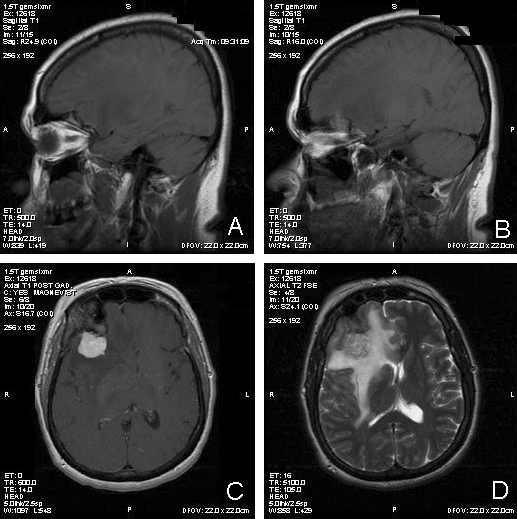

Clinical information The patient was a 54 year-old woman with a history of diabetes. She developed vomiting and frontal headache for two days. As per the descriptions of her family members, she had a few episodes of starring into the left and was unresponsive. The patient described that she could remember all these episodes clearly. On physical examination, the patient was well oriented and alert. There was no weakness in the extremities, ophthalmoplegia, diplopia, reduced visual acuity or facial weakness. An MRI and a CT scan were performed and yielded the following representative images. A surgery was performed. Representative photographs of the specimen are illustrated below.

Com405-1-Imag-1.gif (48010 bytes) Com405-1-Imag-2.gif (49140 bytes) Com405-1-Imag-3.gif (37591 bytes) Com405-1-Imag-4.gif (44330 bytes) Com405-1-Imag-6.gif (109828 bytes)

A. B. C. D. E.

T1-weighed MR images demonstrate an extraaxial, dural based mass involving the right supraorbital region  (Panel A and B). The mass shows homogeneous enhancement  (Panel C). CT scan demonstrates as well as rim calcification (Panel E). On T2-weighed imagers, significant vasogenic edema is demonstrated despite the small size of the lesion and the extraaxial location (Panel D).